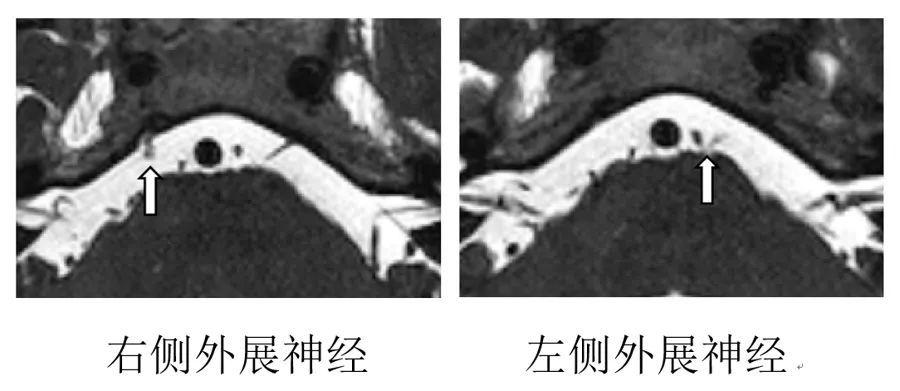

李世亭教授团队通过外展神经薄层磁共振检查发现,患者右侧外展神经完全断裂,左侧外展神经根部因血管压迫导致功能受损。面对全球范围内尚无成熟手术方案的困境,团队结合患者病情创新提出两套手术策略:若断裂端可见,采用神经端端吻合术;若仅存单侧断端,则首创“三叉神经运动根-外展神经吻合术”,通过神经移植重建功能通路。